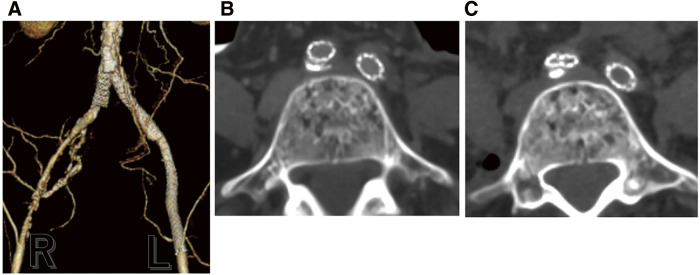

The patient previously underwent surgery for cervical cancer. She reported intermittent claudication, and computed tomography (CT) revealed total occlusion of the left iliac artery. We conducted endovascular treatment (EVT) using balloon-expandable covered stents (BECS). The patient underwent colostomy closure after EVT. The patient reported intermittent claudication beginning the day after the procedure. The CT showed a collapse of the distal side of the stent implanted in the right common iliac artery, accompanied by localized thrombo-occlusion. During open surgery, metal hooks typically affect the iliac artery; force transmission through the tissue may indirectly compress the iliac artery, leading to BECS failure.

患者曾接受过宫颈癌手术。她报告出现间歇性跛行,计算机断层扫描(CT)显示左侧髂动脉完全闭塞。我们使用球囊扩张覆盖支架(BECS)进行了血管内治疗(EVT)。EVT 后,患者接受了结肠造口术。术后第二天,患者出现间歇性跛行。CT 显示,植入右侧髂总动脉的支架远端塌陷,并伴有局部血栓闭塞。在开放手术中,金属钩通常会影响髂动脉;通过组织传递的力可能会间接压迫髂动脉,导致 BECS 失灵。